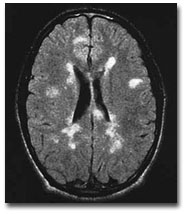

vi. Neuro-imaging including CT, MRI and carotid doppler.

viii. Multiple sclerosis and its ophthalmic manifestations.